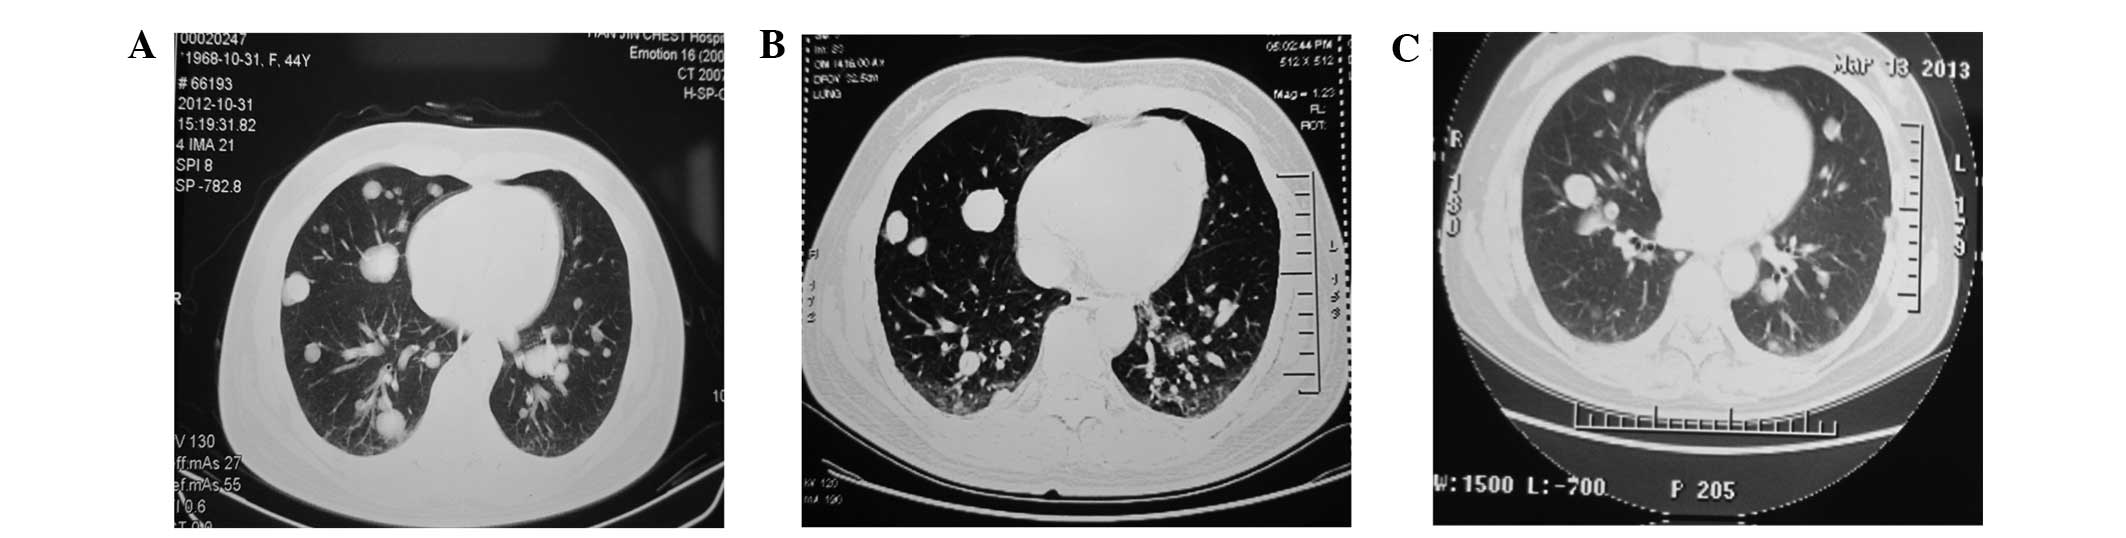

Benign pulmonary metastasizing leiomyoma of the uterus: A case report

Pulmonary benign metastasizing leiomyoma (BML), is characterized by multiple pulmonary nodular lesions and is a rare disease. The present study reports the case of a 45‑year‑old asymptomatic woman who underwent an excision of uterine leiomyoma 11 years previously. Chest computed tomography (CT) revealed multiple bilateral pulmonary nodules five months prior to admission, during a regular check‑up. Intravenous levofloxacin (0.5 g/day) was administered for one week, which demonstrated no effect. Positron emission tomography combined with CT (PET/CT) revealed no evident radioactivity concentration. Due to the suspicion of metastasizing leiomyoma, video‑assisted thoracoscopic surgery, with a wedge resection of the right pulmonary lesion, was performed. Post‑operative pathological examination revealed the lesion to be a pulmonary leiomyoma accompanied by local necrosis. Immunohistochemical staining revealed that the lesion was positive for the expression of smooth muscle actin, desmin, estrogen receptor, progesterone receptor and B‑cell lymphoma‑2. Cytokeratin and epithelial membrane antigen were not expressed in the tumor cells. Staining for Ki‑67 revealed expression of Ki‑67 in ~1% of the spindle cells. The overall morphological and immunohistochemical features, accompanied by the remote patient history of primary uterine leiomyoma, supported the diagnosis of pulmonary BML.

Figure 1